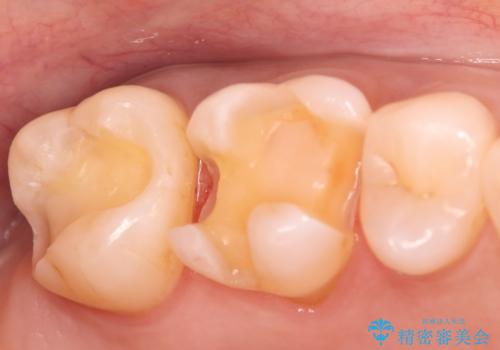

- 昔入れた金属の被せ物を白い物に変えたいと思い来院された患者様です。レントゲン等確認し審美的によく、強度のあるセラミックインレーにて治療いたしました。

審美的に良い補綴物に変わり満足いただきました。かみ合わせも問題なく快適に食事できているとのことでした。